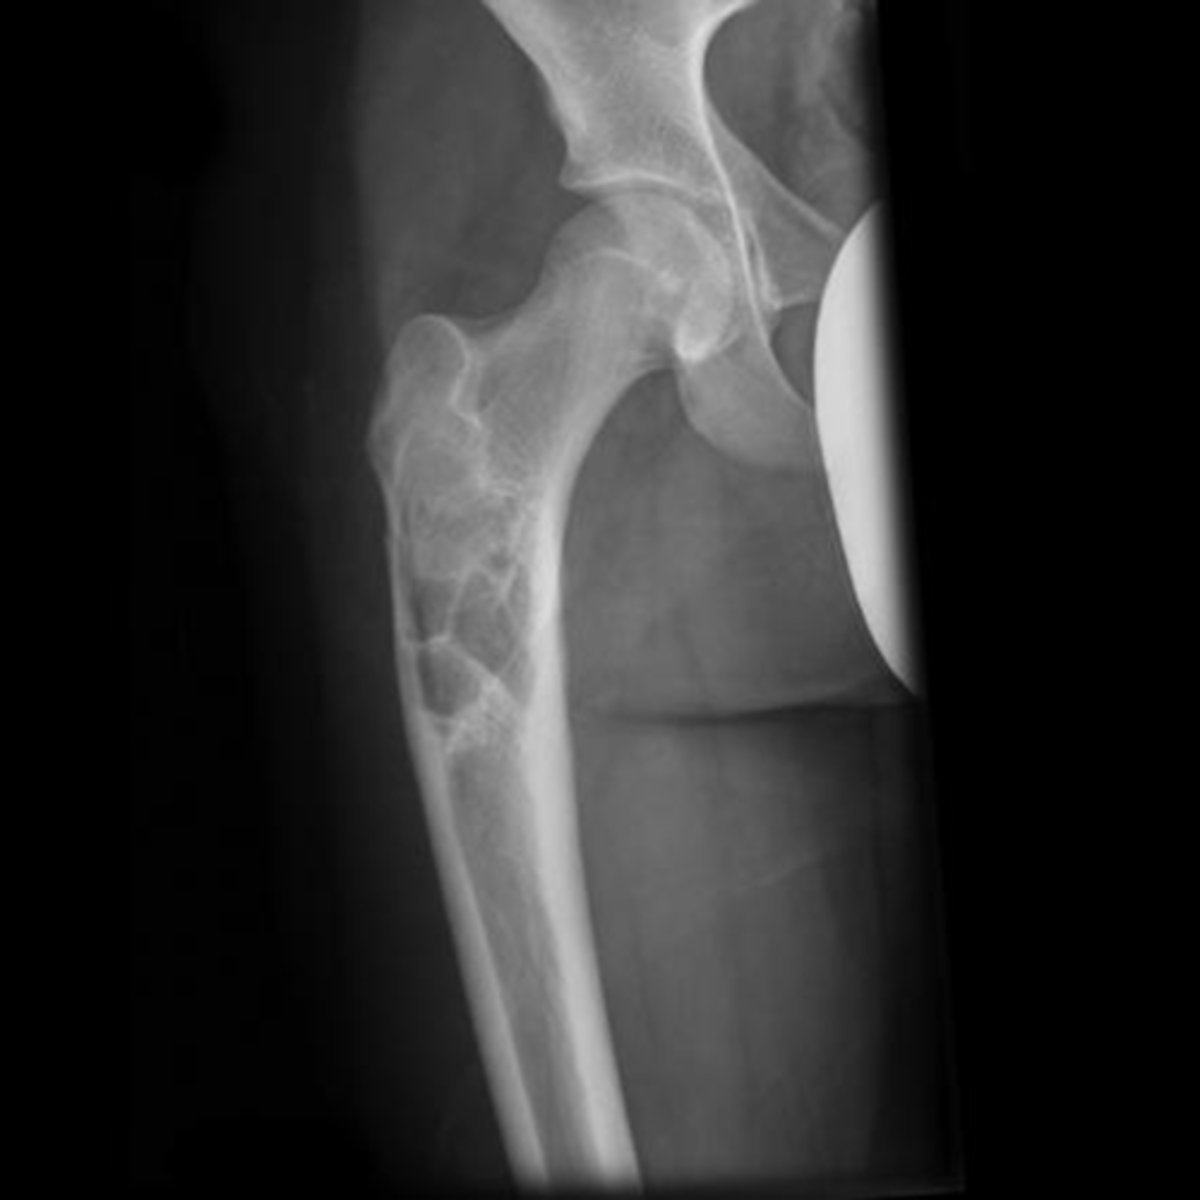

- Osteolytic

- Geographic

- Multiloculated and septated

- Begin in metaphysis

- Extend to subarticular bone

- Expansion

- Eccentric

- Quasi-malignant (can't tell benign from malignant)

State the imaging features of giant cell tumor

<p>State the imaging features of giant cell tumor</p>